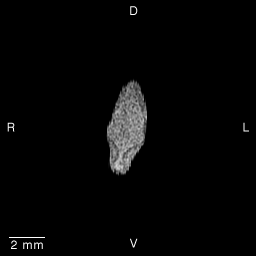

Stage 15 (Day 33), transverse slice 3